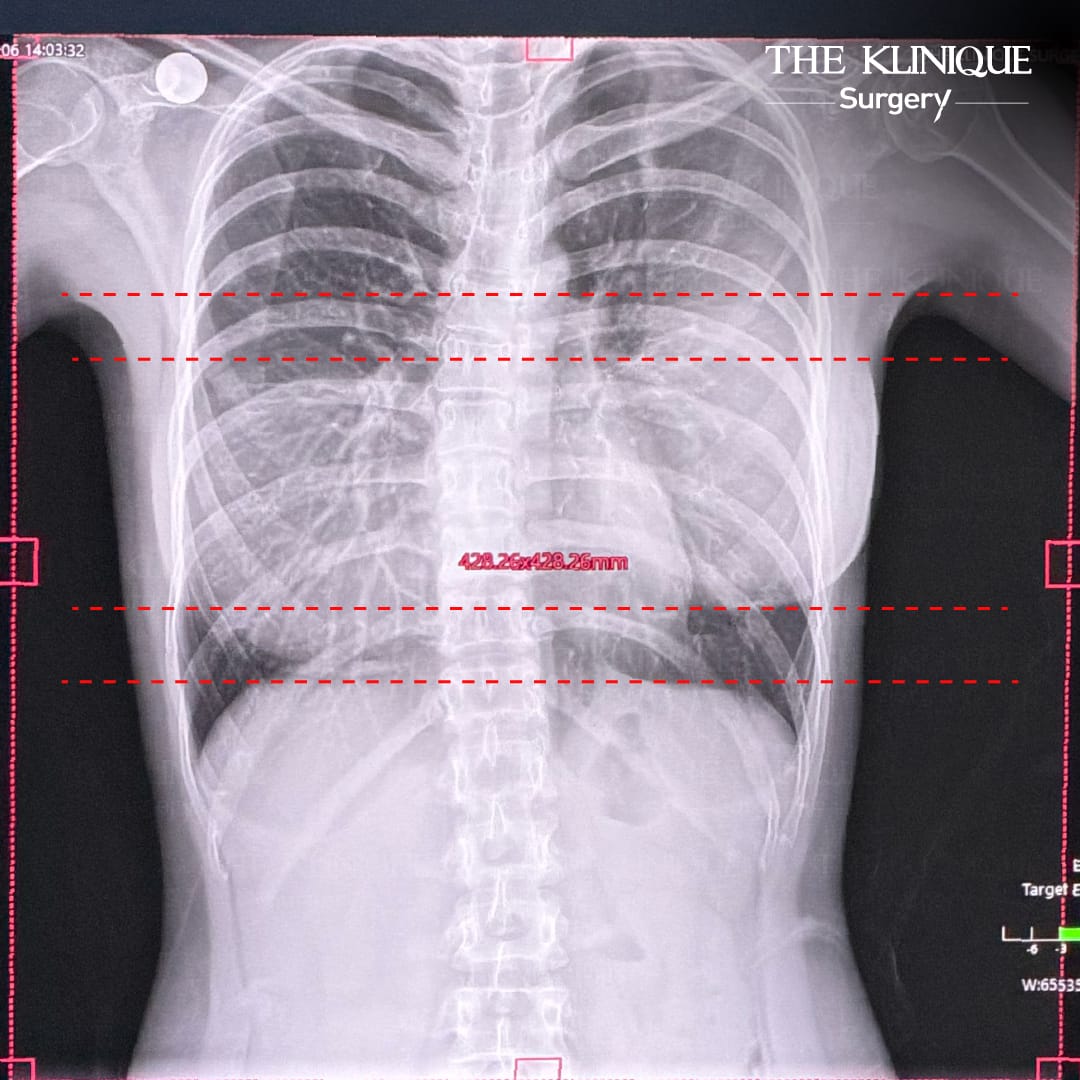

จากที่ได้ทำการปรึกษา ประเมิน จากคุณหมอมุน โดยที่ THE KLNIQUE Surgery ก่อนจะทำการผ่าตัด จะมีการตรวจสุขภาพแบบครบวงจร เรียกได้ว่า ครบจบ สะดวกสบาย และได้มีการทำ x-ray และ Ultrasound ทำให้เห็นชัดเลยว่า หน้าอกมันไม่ได้เป็นทรง แต่เป็นก้อน และมีภาวะพังผืดเกาะแน่น บีบอัดจนซิลิโคนเสียทรง เลยเป็นที่มีของความหน้าอกที่ไม่เท่ากัน

ตอนตรวจว่าช็อกแล้ว ตอนผ่าช็อกยิ่งกว่า เพราะเมื่อคุณหมอมุนได้ทำการผ่าตัดเข้าไปแก้ไขหน้าอก พบพังผืดหนากว่า 1 เซนติเมตร และยังเจอสิ่งแปลกปลอม นั่นก็คือผ้าก็อตอยู่ด้านในอีกด้วย ทนอยู่กับความเสี่ยงมาตลอดเกือบ 3 ปี ทั้งเจ็บ ทั้งปวด อกเบี้ยว นมไม่เท่ากัน และยังหวิดเสี่ยง ทิ้งไว้นานๆ อันตรายเกือบถึงชีวิตได้เลย

คุณหมอมุนได้อธิบายไว้เพิ่มเติมว่า สาเหตุของหน้าอกไม่เท่ากัน อาจเกิดจากภาวะ Capsular Contracture พังผืดรัดรอบถุงเต้านม จนทำให้เสียทรง หน้าอกแข็ง สองข้างมีขนาดไม่เท่ากัน มีความดันสูงขึ้นกว่าอีกข้าง ความนิ่มของซิลิโคนน้อยลง มีอาการปวดตึง และเจ็บแปลบๆ เป็นระยะ และบางรายอาจมีอาการบวมแดง เพราะเกิดจากการอักเสบด้านใน